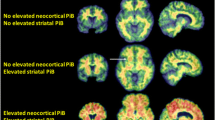

This is a report of new case of PIBI(D)S, a rare autosomal recessive syndrome characterized by photosensitivity, ichthyosis, brittle sulfur-deficient hair (trichothiodystrophy), impaired intelligence, decreased fertility, and short stature. Bilateral cataract and axial osteosclerosis were also detected. Magnetic resonance imaging (MRI) revealed diffuse central nervous system dysmyelination, a finding also described in the only three other reported cases in which MRI was performed. The paper also considers certain similarities in neurological signs and neuroradiological findings between PIBI(D)S, Cockayne syndrome, and xeroderma pigmentosum β all of which are inherited diseases characterized by photosensitivity and DNA repair defect.

Peserico A, Battistella PA, Bertoli P (1992) MRI of a very rare hereditary ectodermal dysplasia: PIBI(D)S. Neuroradiology 34:316β317